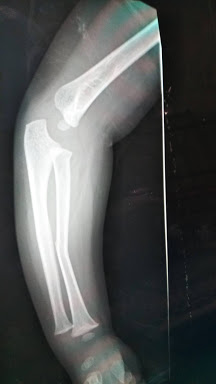

やらかしましたっ!骨折!!

題名の通り、

腕を骨折

しました!

わかりづらいですねぇ。。。

じゃあ、載せるな!!というツッコミは置いといて・・・

やらかしましたのは

弟

くんです。

夜の9時

にソファーのTOPから落ちました(°□°;;;)

肘下が曲がっていたので、一応

救急病院

へ。

診察は

全治1ヶ月

といったところでした。

子供の骨は柔らかいそうで、

ポキッ

と折れることはなく、

グニャッ

と曲がっちゃうようです。が、これからまだまだ腕も成長してくるので、その過程でほとんど真っ直ぐになっていくようです。